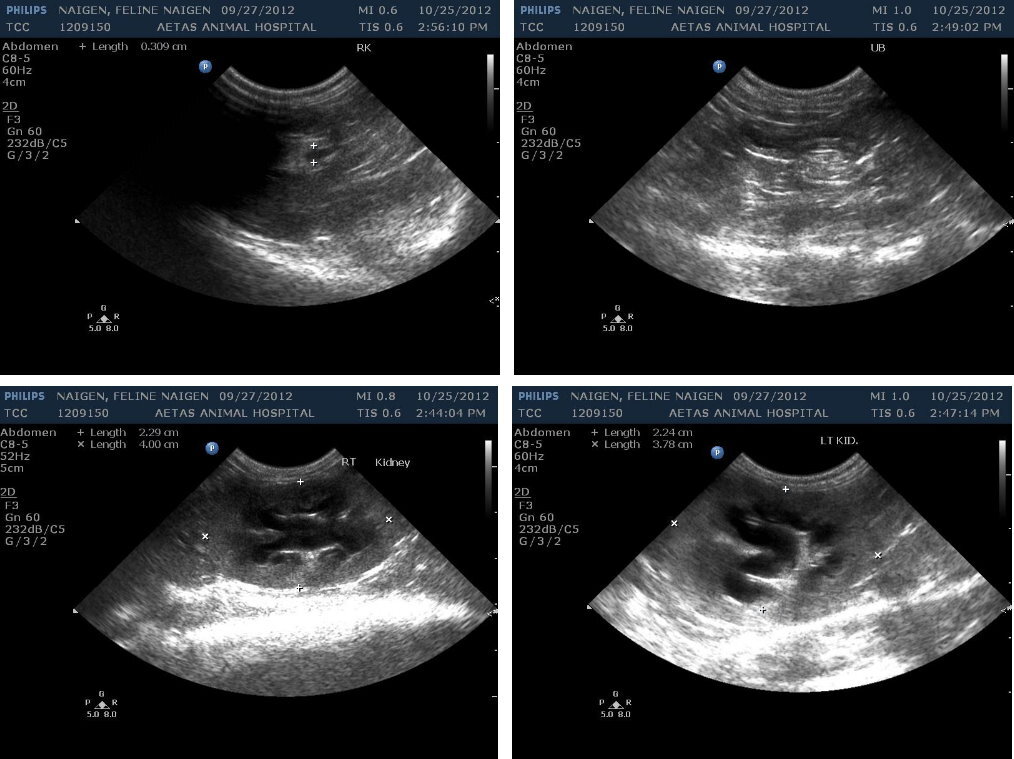

10/25奶精精神食慾變差,驗血發現腎指數BUN 71 / CREA 4.3均高出正常值許多,掃超音波發現腎臟腫大有水腎現象,輸尿管擴張且開始出現無尿的現象,晚間再度驗血BUN 91 / CREA 4.6指數繼續攀升,且鉀離子K+已高至危及性命,疑似輸尿管阻塞因此決定立即進行緊急開腹探查手術。

術中發現雙側的輸尿管漲大,雙側的腎臟後方可以看到明顯的手術結,獨立並未與組織沾黏,不過於輸尿管靠近膀胱部分發現輕微的沾黏,經由剝離後輸尿管腫脹程度減緩,術後鉀離子以及腎指數也有顯著的改善。